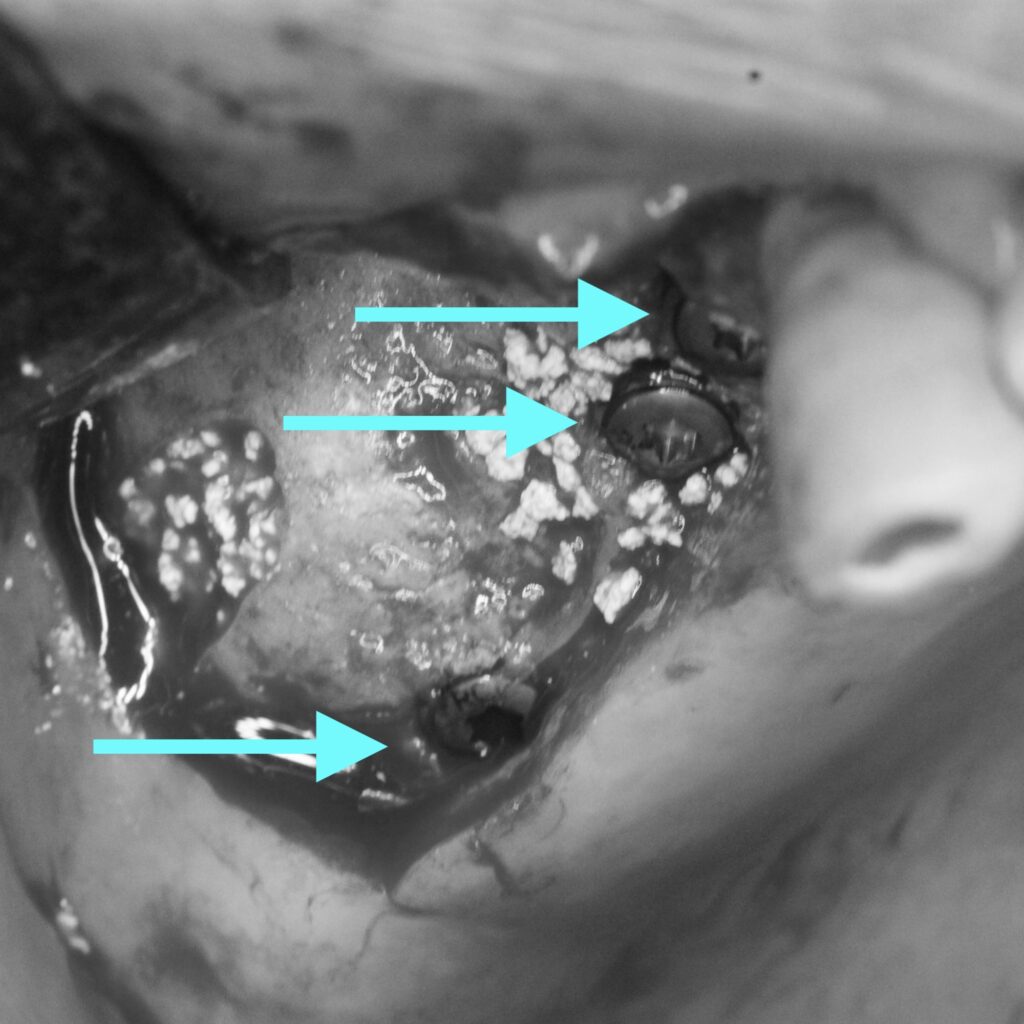

インプラントを希望されたため、右上に1本、右下に2本のインプラント治療を行いました。

手術後、仮歯で経過観察し問題が出ない事を確認。

型取り後、セラミックを装着しました。